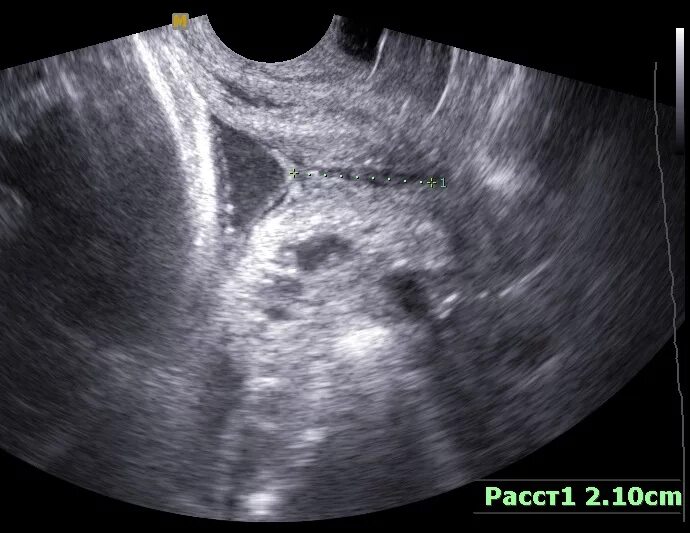

Внутренний зев воронкообразно